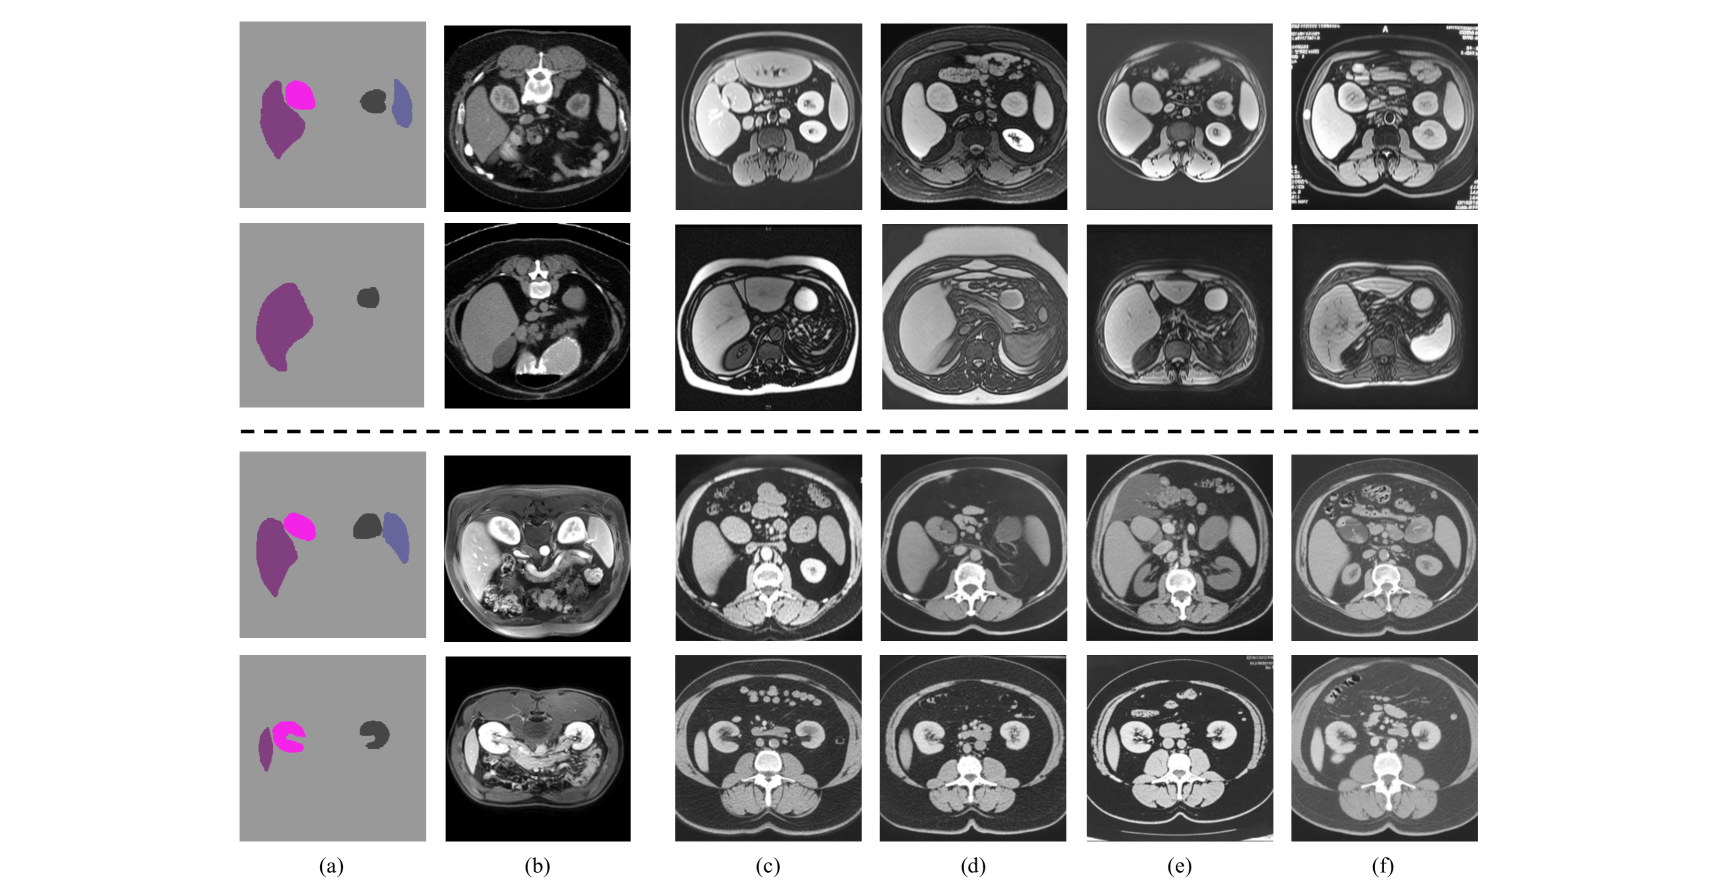

We also visualize the segmentation results of our method and other DG approaches for all tasks in Fig. 3Fig. 4 and Fig. 5, respectively. The first two columns show source and target domain images, illustrating the domain shift. We can see that the segmentation masks in the unseen target domain produced by our method exhibit greater accuracy and improved spatial continuity of the foreground compared to the baselines.

\begin{overpic}[width=216.81pt]{Figs/fig3.pdf} \put(2.8,0.5){\color[rgb]{0,0,0}\tiny{Source}} \put(15.25,0.5){\color[rgb]{0,0,0}\tiny{Target}} \put(25.0,0.5){\color[rgb]{0,0,0}\tiny{MixStyle}} \put(35.1,0.5){\color[rgb]{0,0,0}\tiny{RandConv}} \put(46.1,0.5){\color[rgb]{0,0,0}\tiny{DualNorm}} \put(58.5,0.5){\color[rgb]{0,0,0}\tiny{CSDG}} \put(69.25,0.5){\color[rgb]{0,0,0}\tiny{SLAug}} \put(81.0,0.5){\color[rgb]{0,0,0}\tiny{Ours}} \put(89.0,0.5){\color[rgb]{0,0,0}\tiny{Ground Truth}} \end{overpic}

Figure 3: Visualization of segmentation results on the AS task.. First two rows: “CT to MRI” task; Last two rows: “MRI to CT”.